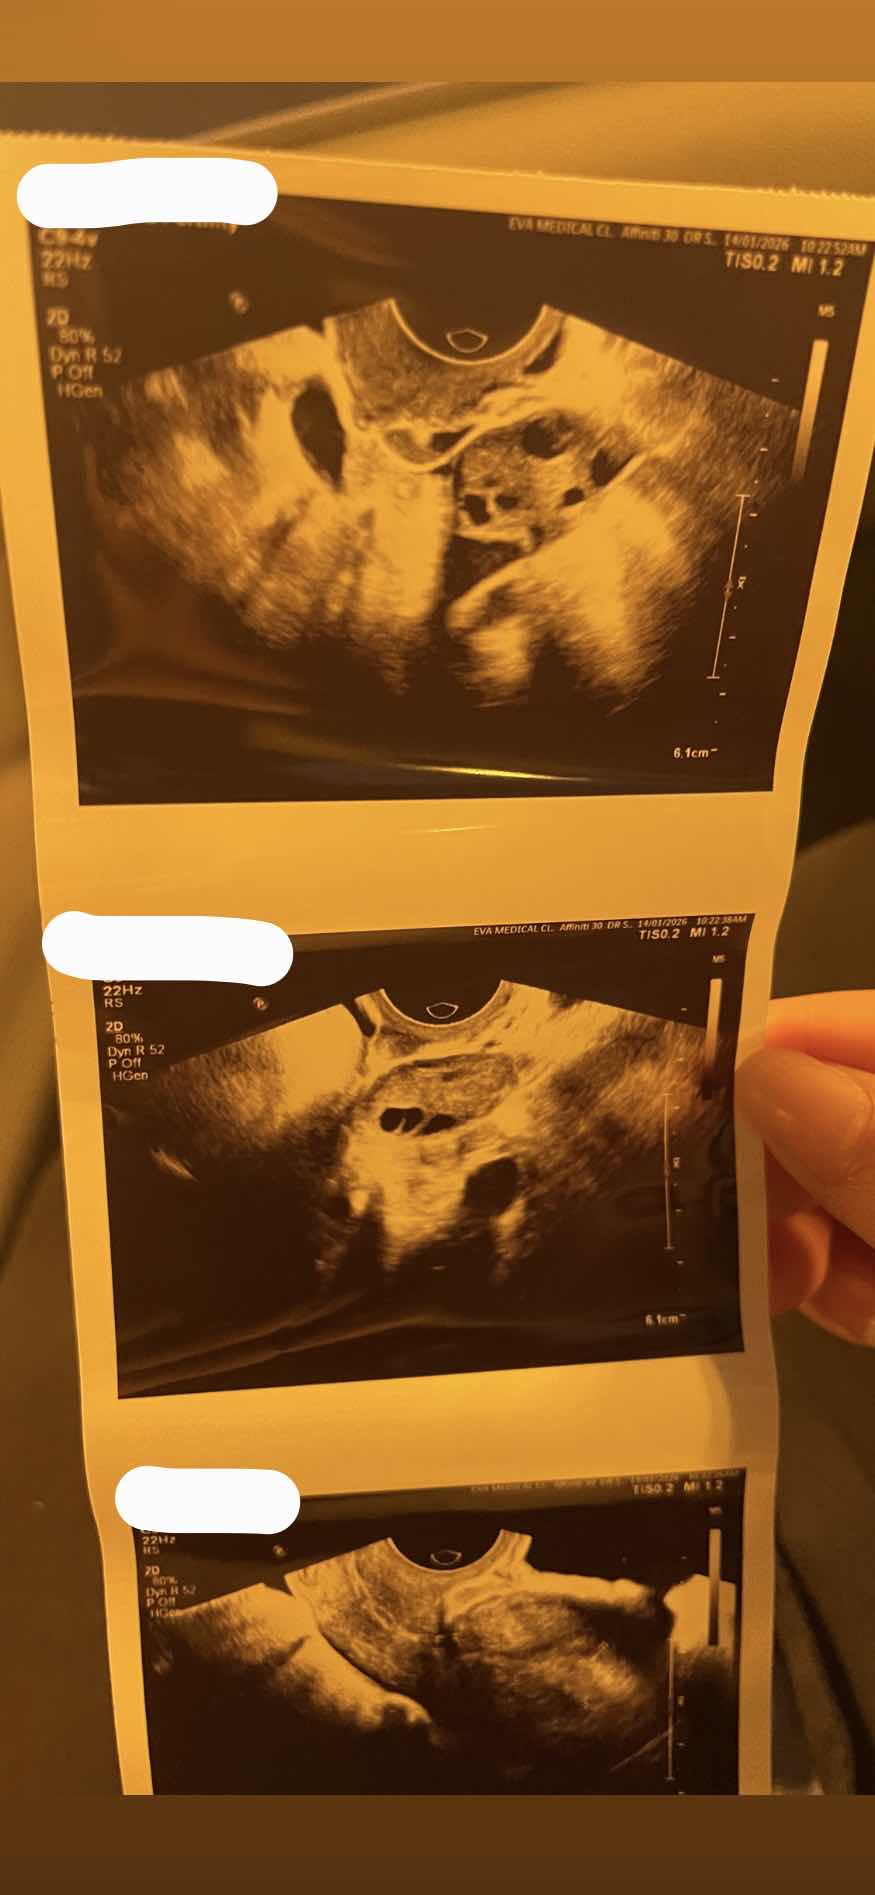

عمري٣١ سنه ، هل حجم البويضات جيد ام لا حسب السونار المرفق؟ لاني اريد الحمل وهل استطيع الاستغناء عن فحص قناة فالوب؟ لاني خائفة من الم اشعة الصبغة مع العلم لدي ابنه واحده عمر٣ سنوات

البويضات ليست كافية 0 2026-01-20T09:31:21+00:00 2026-01-20T09:31:21+00:00

البويضات ليست كافية